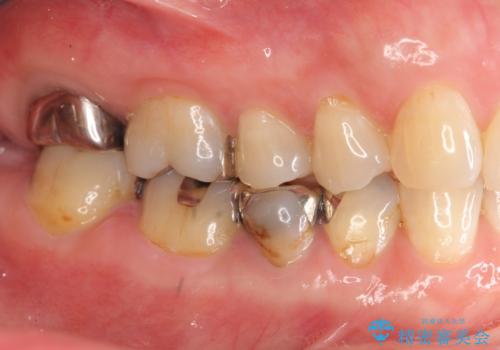

- 「 銀歯が原因で皮膚にアレルギー症状が出ている。」、と皮膚科のかかりつけ医に言われメタルフリー治療を希望され来院されました。

拡大鏡下で丁寧に銀歯の除去を行ったのち、金属を用いないセラミックインレー・クラウンによる治療を行います。